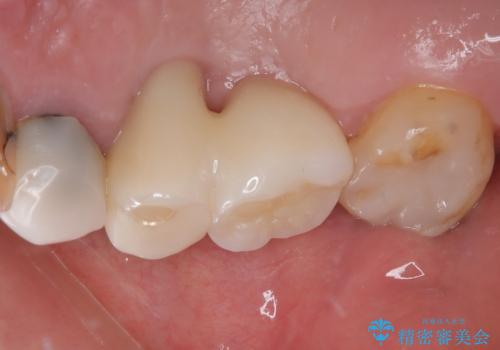

本来であれば、下顎の歯列を整えることで、上下がタイトに咬み合わせるように仕上げるべきでしたが、予算の都合で上顎のインプラント補綴治療のみを行うこととなりました。